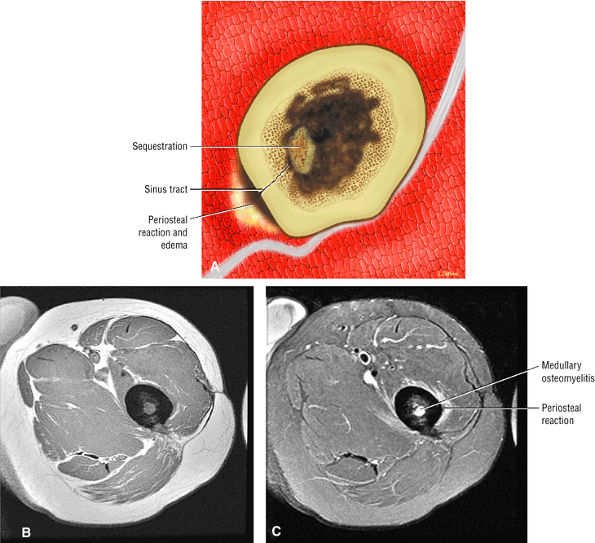

![]() |

|

FIGURE 3.121 ● A graph of the muscle T2 relaxation times before (day 0) and after (days 1, 3, 5, 10, 25, 40, 50, 60, and 80) exercise involving eccentric actions. There was a statistically significant (P < 0.05) increase in T2 relaxation times for each subsequent postexercise imaging interval compared with T2 relaxation times before exercise (day 0). Values are given as means plus or minus the standard deviation. The “T” lines at the top of each bar represent the plus range of the standard deviation.

between cramp, with its high-frequency action potentials, and contracture is basic (Fig. 3.123).134,145 Muscle contracture occurs most often in metabolic disorders such as inherited defects of glycolytic enzymes (e.g., myophosphorylase deficiency or McArdle—s disease).134,145,150 After the contracture, patients typically develop elevated serum creatine kinase levels and, when severe, pigmenturia and acute renal failure. During the contracture, there typically is intense pain. In some diseases, such as phosphofructokinase deficiency, patients may have few or no symptoms and yet have marked rhabdomyolysis. In these patients, MR imaging may show extensive zones of myonecrosis and fatty infiltration.134,145,150 Although not specific, the coexistence of muscle edema, atrophy, and fatty infiltration is a significant finding and strongly suggestive of a myopathic or neurogenic disorder.134,145

FIGURE 3.122 ● Delayed-onset muscle soreness. T2-weighted axial images obtained from the middle upper arms of five different subjects on day 5 after performing biceps curl exercises involving eccentric actions. Note the variability in the pattern of increased signal intensity affecting the biceps and brachialis muscles. (TR/TE, 2000/80 msec)